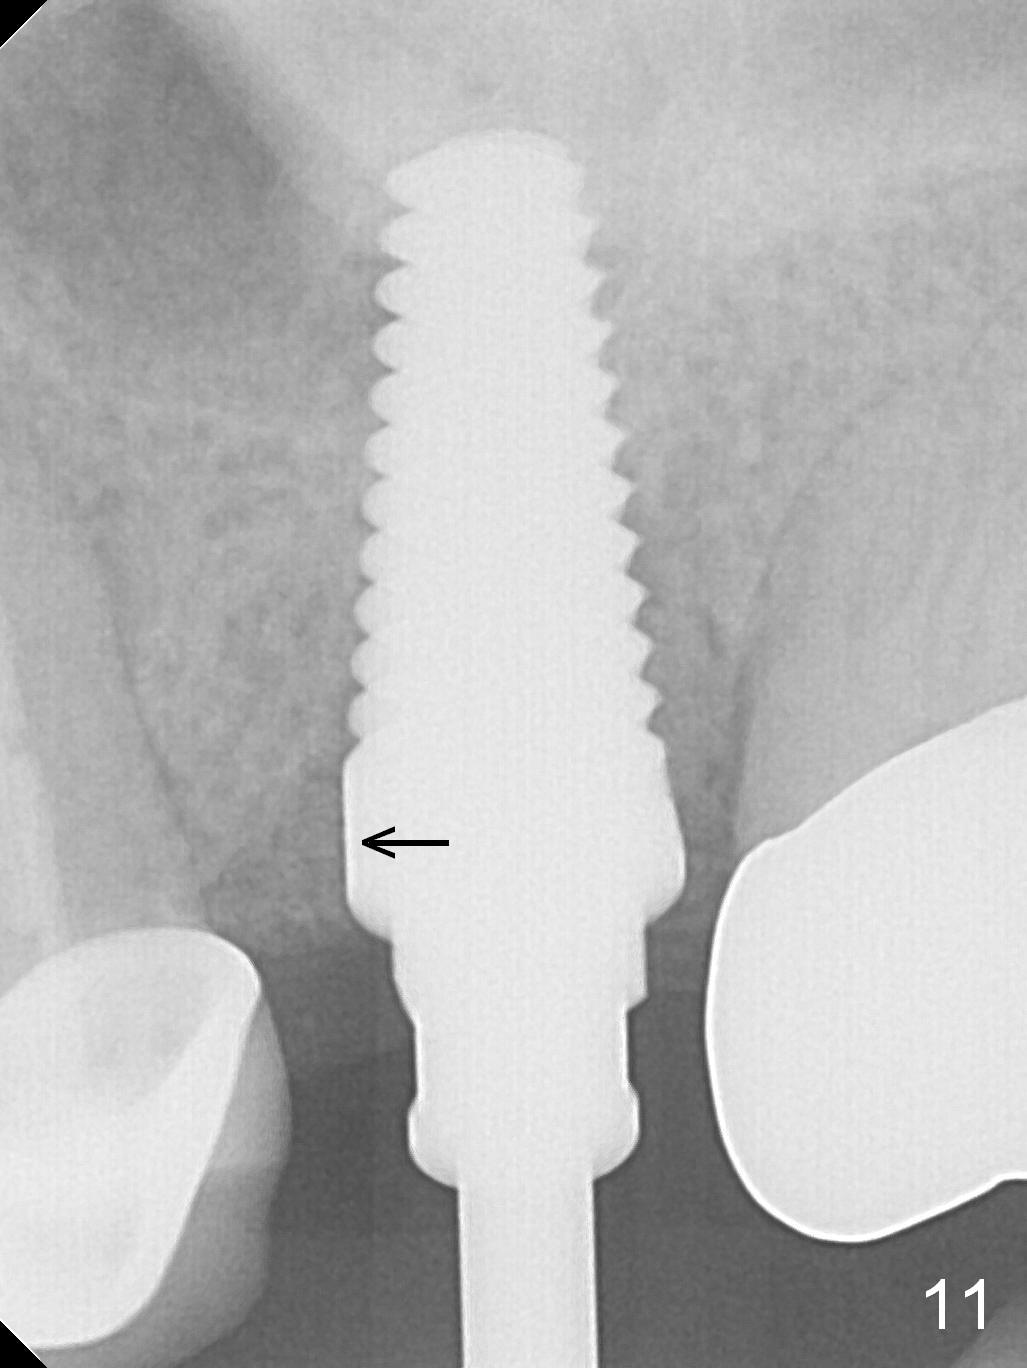

The patient is doing well 9 days postop.  The immediate provisional is loose and over-sized.  It is removed for trimming and reline; the socket and bone graft (Fig.8 *) are healing.  It appears that an angled abutment is required next time of provisional revision.  When an angled abutment is being placed 23 days postop (Fig.9), it appears to wiggle the implant due to its long leverage.  Instead a healing abutment is placed.  The implant is unstable 4.5 months postop with seemingly excessive bone-implant gap (Fig.10 <).  The 5.5x9 mm implant is removed.  A 5x17 mm tap is used to change the trajectory and sinus lift, followed by 6x17 one (Fig.11).  Finally a 6x14 mm tissue-level implant is placed with insertion torque > 50 Ncm (Fig.12; vs. <20 Ncm (Fig.7,10)) and improved trajectory.  An immediate provisional is fabricated to prevent the mesial drifting of the tooth #15 (Fig.13 P (*: occlusal clearance)).  By using the taps and placing the longer implant, the sinus lift is more obvious (compare Fig.10 and 12 (*)).  Sinus lift remains evident 3.5 months postop (Fig.14) with apparently osteointegration (Fig.15).